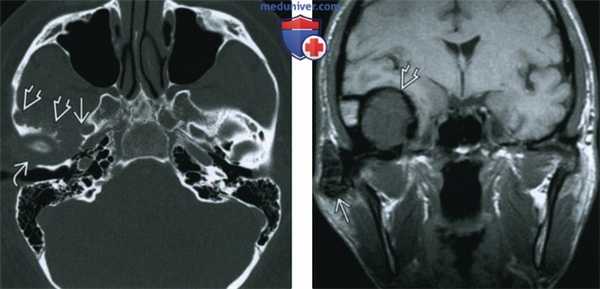

(Слева) При аксиальной КТ в костном окне определяется расширение суставного пространства правого височно-нижнечелюстного сустава, также видны множественные эрозии округлой формы в прилежащих отделах основания черепа с поражением скуловой дуги и большого крыла клиновидной кости выше наружного края овального отверстия.

(Справа) При МРТ Т1ВИ в корональной проекции визуализируется гипоинтенсивное объемное образование правого ВНЧС с «ободком» низкой сигнальной интенсивноаи. Также визуализируется гипоинтенсивное экстрааксиальное объемное образование в средней черепной ямке, тесно прилежащее к интракраниальным структурам, с таким же гипоинтенсивным «ободком» по периферии.

(Справа) При МРТ Т1ВИ в корональной проекции визуализируется гипоинтенсивное объемное образование правого ВНЧС с «ободком» низкой сигнальной интенсивноаи. Также визуализируется гипоинтенсивное экстрааксиальное объемное образование в средней черепной ямке, тесно прилежащее к интракраниальным структурам, с таким же гипоинтенсивным «ободком» по периферии. (Слева) При MPT T1BИ FS с КУ в аксиальной проекции, выполненной пациенту с пигментным ворсинчато-узелковым синовитом (ПВУС), в расширенном суставном пространстве правого ВНЧС и вокруг него визуализируются многочисленные узлы с гипоинтенсивным сигналом. Обратите внимание, что контрстаное усиление выражено минимально.

(Слева) На аксиальной КТ в костном окне определяется расширение суставного пространства правого ВНЧС с наличием множественных округлых эрозий прилежащих отделов основания черепа с вовлечением внутреннего края скуловой дуги и большого крыла клиновидной кости вплоть до наружного края овального отверстия.

(Справа) На корональной МРТ (Т1 ВИ) определяется гипоинтенсивное объемное образование В правого ВНЧС с «ободком» на периферии еще более низкой интенсивности, продолжающееся во внемозговое объемное образование средней черепной ямки с похожим ги-поинтенсивным «ободком» на периферии.